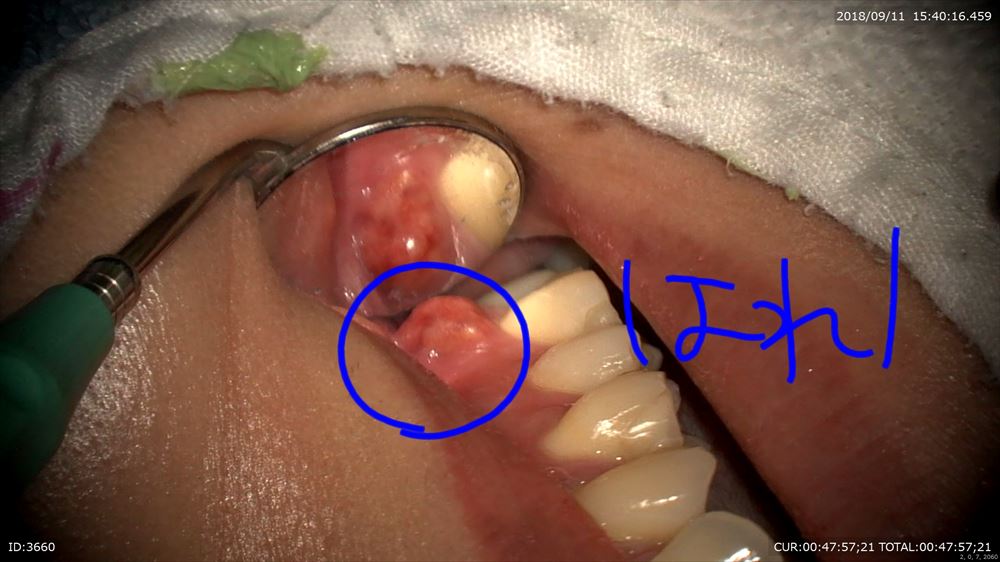

こんなに重症根の先の膿が歯茎から出てきた!重症の虫歯

でも丁寧にマイクロスコープを使用